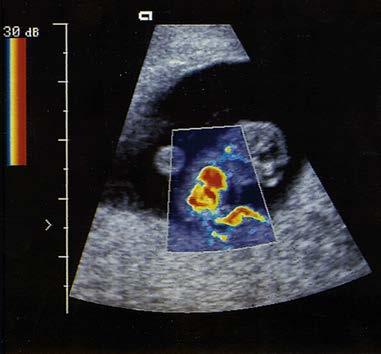

enable color-coded 2D and 3D presentations of Doppler information (color-Doppler displays) to be superimposed on gray-scale anatomic images (Figure 1-13). Doppler information is applied to loudspeakers for audible evaluation and to spectral-Doppler displays for quantitative analysis (Figure 1-14). The spectral-Doppler operation includes

anatomic imaging to determine the location(s) from which the spectral information is acquired (Figure 1-15).

FIGURE 1-13 Color-Doppler displays of blood flow. Presented in forms called (A) colorDoppler shift, (B) color-Doppler power, and (C) three-dimensional color-Doppler power displays.